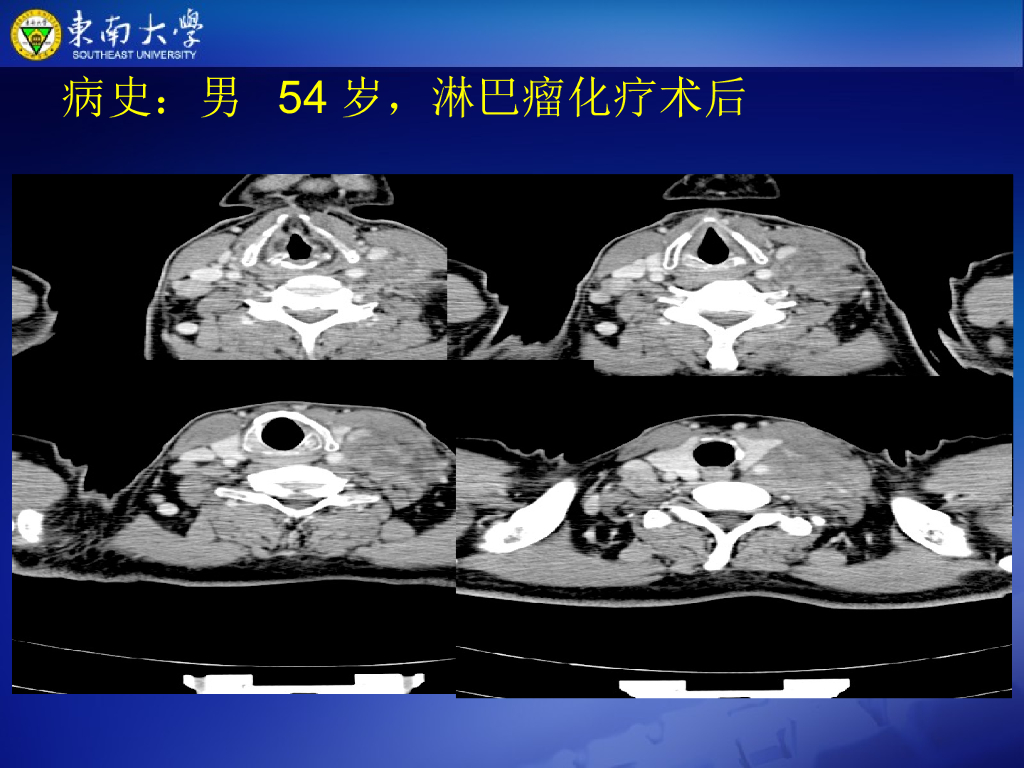

《放射诊断学》演示文稿-颈部病变--实习.pdf